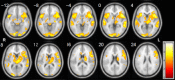

Presurgical language mapping for patients with lesions close to language areas is critical to neurosurgical decision-making for preservation of language function. As a clinical noninvasive imaging technique, functional MRI (fMRI) is used to identify language areas by measuring blood-oxygen-level dependent (BOLD) signal change while patients perform carefully timed language vs. control tasks. This task-based fMRI critically depends on task performance, excluding many patients who have difficulty performing language tasks due to neurologic deficits. On the basis of recent discovery of resting-state fMRI (rs-fMRI), we propose a "task-free" paradigm acquiring fMRI data when patients simply are at rest. This paradigm is less demanding for patients to perform and easier for technologists to administer. We investigated the feasibility of this approach in right-handed healthy control subjects. First, group independent component analysis (ICA) was applied on the training group (14 subjects) to identify group level language components based on expert rating results. Then, four empirically and structurally defined language network templates were assessed for their ability to identify language components from individuals' ICA output of the testing group (18 subjects) based on spatial similarity analysis. Results suggest that it is feasible to extract language activations from rs-fMRI at the individual subject level, and two empirically defined templates (that focuses on frontal language areas and that incorporates both frontal and temporal language areas) demonstrated the best performance. We propose a semi-automated language component identification procedure and discuss the practical concerns and suggestions for this approach to be used in clinical fMRI language mapping.